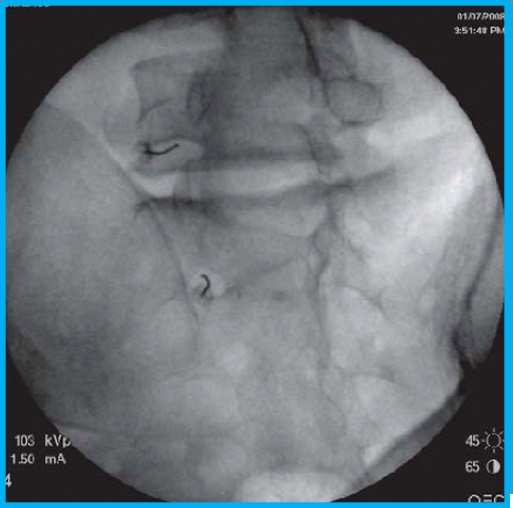

Πρόκειται για μια ελάχιστα επεμβατική τεχνική λύσης μετεγχειρητικών συμφύσεων με εισαγωγής ενός εύκαμπτου ενδοσκοπίου στην οσφυϊκή μοίρα μέσω του ιερού τρήματος. Με χρήση διαλύματος υαλουρονιδάσης και φυσιολογικού ορού επιτυγχάνεται οι λύση συμφύσεων, με σύγχρονη απελευθέρωση των νευρικών δομών.